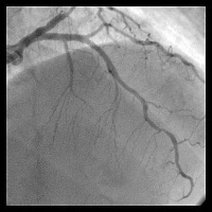

手把手教你做冠脉造影- 5.0共3页

- 手把手教你做冠影现段,冠状动影仍然是冠心病断的手段,为实现今天做影,明天就上班的安全、准确,熟练掌握冠状动影技术是中之。作|大军孔令秋来源|孔瘦本期,我们用步步为